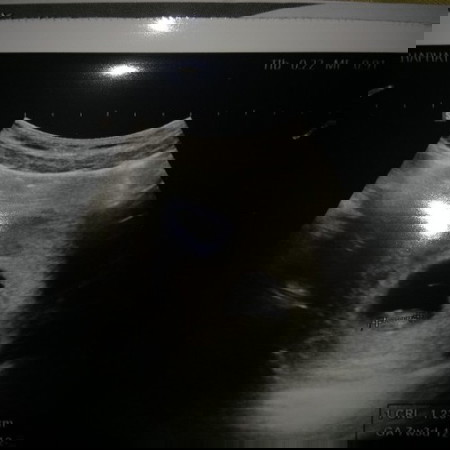

อายุครรภ์7สัปดาห์ 1.23cm

ถือว่าปกติไหม๊ค่ะ

ตารางนี้เป็นเกณฑ์เฉลี่ยค่ะคุณแม่ เราว่าน้องปกตินะคะ